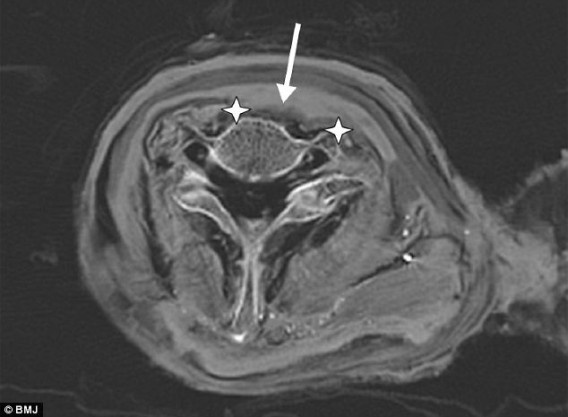

ラムセス3世のミイラのCT画像によると、王の気管と主幹動脈は裂けており、傷は左右7センチにわたり、深さは脊椎にまでほぼ達していたことが分かった。またこの傷によって、首の前面部の軟組織は完全に傷んでいた。

右下顎頸部領域の下の皮膚のしわ(矢印)から、絞殺された可能性も高い。